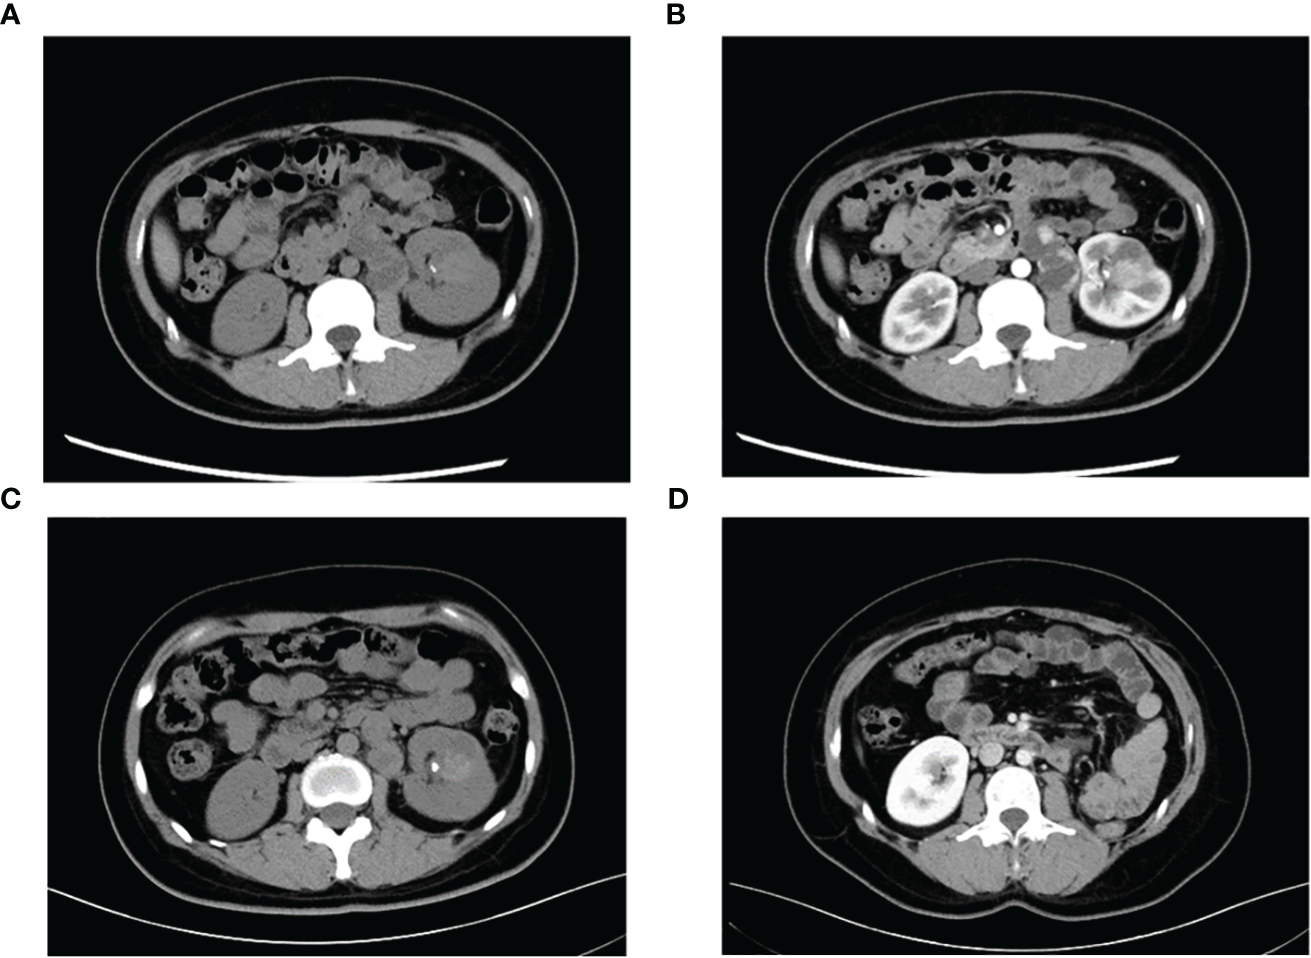

A 29-year-old female presented with painless and gross hematuria and no other symptoms or medical history were found. The patient had no prior history of malignancies and the results of urine exfoliative cytology ruled out uroepithelial carcinoma. A computed tomography (CT) scan revealed a solid-cystic tissue density lesion with calcification measuring 3.2 x 2.8 cm at the ventral middle and lower poles of the left kidney (Figure 1A). The solid component demonstrated moderate enhancement in the corticomedullary phase (Figure 1B). In addition to the primary tumor, a suspected metastasis was observed at the left retroperitoneum with a diameter of approximately 4.6 x 2.4 cm. No metastases present at other sites. Due to the patient’s young age, a specific type of kidney cancer could not be excluded. Therefore, a left renal puncture biopsy was performed, and the pathology morphology was examined using hematoxylin-eosin (HE) staining, which revealed hyaline eosinophilic cytoplasm with papillary structures and psammoma bodies (Figures 2A, B). Additionally, strong positive nuclear immunohistochemical staining of TFE3 was observed (Figure 2C). Immunohistochemically, negative results were observed for CAIX, CK7, and ALK, while CD10 and PAX8 are positive (Figure 2D). TFE3-rearranged RCC could not be excluded; thus, a TFE3 break-apart FISH was performed, which confirmed the diagnosis of TFE3-rearranged RCC (Figure 2E). To further clarify the molecular type, targeted next-generation sequencing was performed, and the final diagnosis of ASPSCR1-TFE3 fusion translocation RCC was confirmed (Figure 3).

Figure 1

Representative CT images of TFE3-rearranged RCC patients. (A) High-density lesions with scattered calcifications (arrows) in the lower pole of the left kidney were observed on plain scan; cystic-solid suspicious metastases (triangles) were observed in the retroperitoneum. (B) Moderate enhancement of the left renal lesion and suspicious metastases was observed during the enhanced phase, and the degree of enhancement was lower than that of the adjacent renal cortex. (C) Lesions and metastases were significantly reduced after neoadjuvant therapy. (D) Postoperative reexamination showed no recurrence of tumor metastasis.

The main indications for neoadjuvant therapy for RCC are: First: High-risk bilateral RCC and isolated RCC. Second: Locally progressive RCC in poor general condition that cannot tolerate surgery for the time being. Third: Patients with high-risk RCC. Fourth: RCC combined with thrombus (8, 9). TFE3-rearranged RCC, as a high-risk tumor, often experiences short-term tumor progression even after patients undergo surgical treatment. Considering that the patient is typically young and the tumor type is quite unique, pure surgical treatment may not achieve satisfactory therapeutic results. In recent years, neoadjuvant therapy has demonstrated promising efficacy in advanced kidney cancer. Therefore, after thorough communication with the patient and their family, it is advisable to consider neoadjuvant therapy as the initial approach rather than immediate surgery. On one hand, preoperative neoadjuvant therapy is expected to reduce the size of the tumor and retroperitoneal metastasis lesions, creating a more favorable time for subsequent surgery. On the other hand, it can provide valuable guidance for postoperative drug treatment choices. The patient underwent neoadjuvant therapy with VEGFR-TKI axitinib (5 mg orally once daily) as first-line treatment to reduce the size of the tumor lesion and metastasis. High PD-L1 expression was observed in the PD-L1 immunohistochemistry analysis (Figure 2F), which is consistent with previous studies that showed the correlation between PD-L1 expression levels in tumor tissues and the efficacy of PD-1 antibody treatment for TFE3-rearranged RCC (10, 11). Therefore, we administered the anti-programmed cell death-1 antibody tislelizumab (200 mg intravenously once every 3 weeks) targeted therapy. After 8 months of neoadjuvant therapy, the tumor and metastasis sizes decreased by 16% (3.2 × 2.8 cm vs. 2.7 × 2.4 cm) and 30% (4.6 × 2.4 cm vs. 3.2 × 2.2 cm), respectively, compared to their original sizes (Figure 1C). In July and August 2021, the CT scan showed no further decrease in the tumor and metastasis sizes after neoadjuvant therapy. As a result, laparoscopic left radical nephrectomy and retroperitoneal metastasis dissection were performed in August 2021. During the surgery, we did not find any evidence of tumor invasion into the adrenal tissue. Therefore, we did not perform an adrenalectomy.

The tumor was classified as IV (pT3aN0M1) based on the pathologic stage of the American Joint Committee on Cancer (AJCC, 8th edition, 2017). The postoperative pathology revealed that the tumor was WHO/ISUP grade 4, and it appeared as a distinct papillary structure (Figure 4A). The HE staining confirmed that the metastatic foci were composed of tumor tissues (Figure 4B). Additionally, the FISH test showed that most tumor nuclei had separated red and green signals, indicating a rearrangement of the TFE3 gene. The patient suspended tislelizumab therapy due to impaired liver function more than a month after the surgery and continued taking VEGFR-TKI. In September 2021, the patient resumed neoadjuvant therapy with axitinib and tislelizumab. The systemic therapy timeline is presented in Figure 5. As of now, the patient has survived for 30 months post-surgery and remains in stable condition without any recurrence of tumor or distant metastases (Figure 1D).